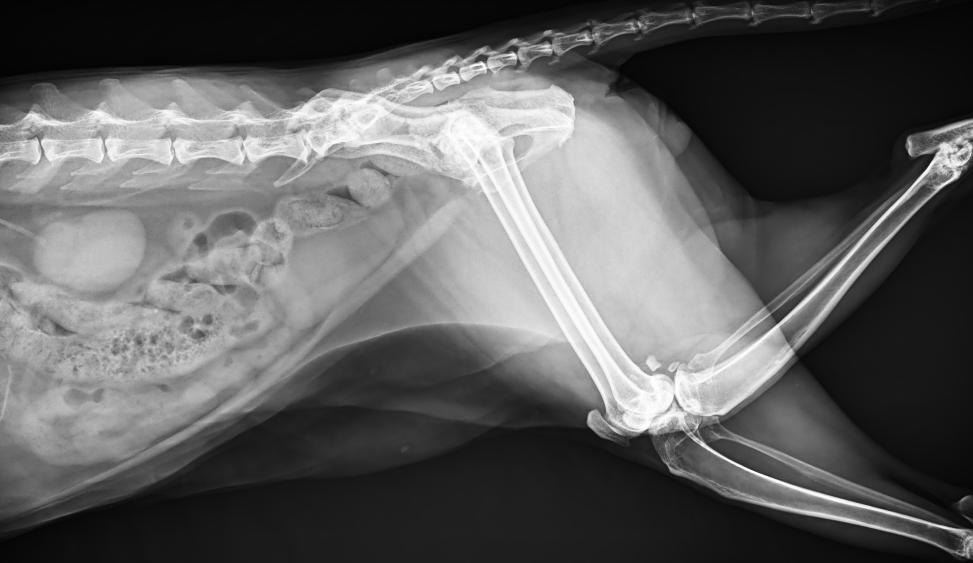

專為拍攝寵物設(shè)計 VET1900 寵物DR

● 17*17大尺寸平板探測器,獲得高質(zhì)量圖像

● 優(yōu)異的空間分辨率及信噪比,提升圖像質(zhì)量

● 采用線噪聲消除技術(shù),使成像質(zhì)量提升40%

● 智能高效的圖像處理軟件,大幅提升圖像質(zhì)量